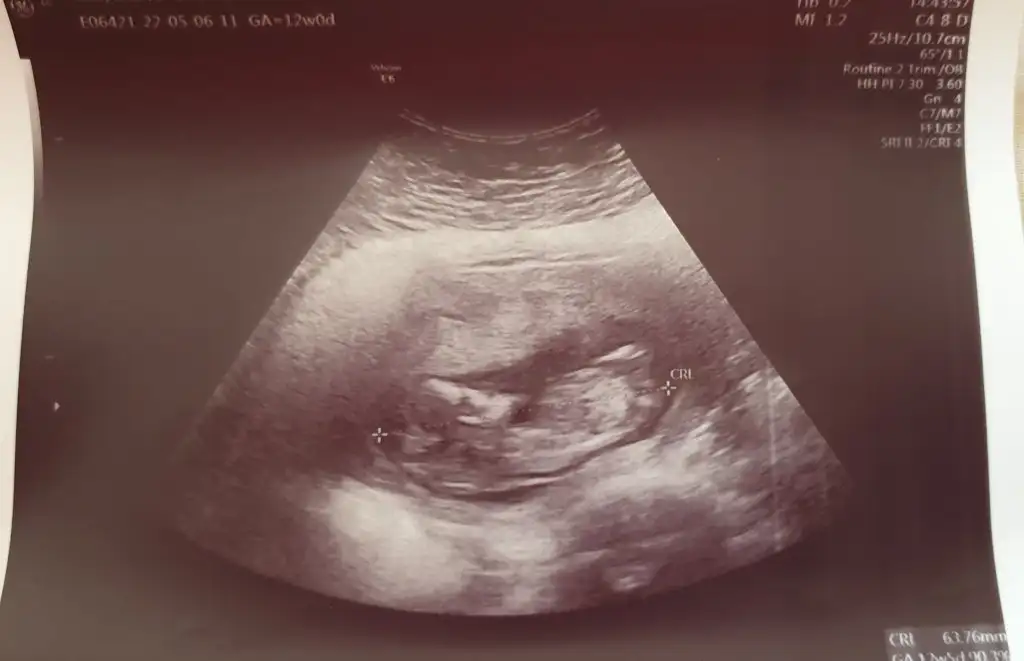

Yine geldim buralara 12. hafta karın ultrasonundan 😅